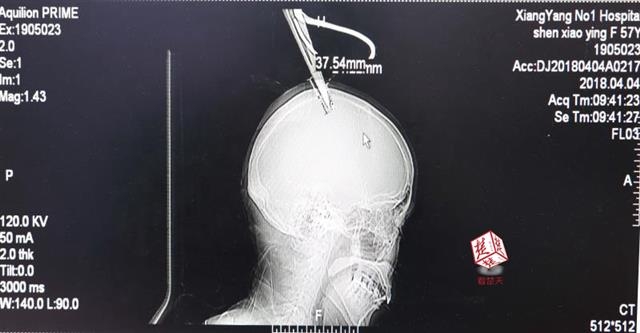

4月4日清晨,襄陽(yáng)市樊城區(qū)太平店鎮(zhèn)57歲的農(nóng)村婦女沈某,在采摘香椿嫩芽時(shí),綁在竹桿上的剪刀因竹子腐朽不慎折斷,剪刀斜插入頭顱。經(jīng)過(guò)及時(shí)搶救,目前脫離生命危險(xiǎn)。

醫(yī)生檢查發(fā)現(xiàn),剪刀刀尖斜嵌在沈某顱骨里,離腦髓只有兩三毫米。所幸是斜著插進(jìn)去,如果是垂直刺入,很有可能造成癱瘓。

醫(yī)生檢查發(fā)現(xiàn),剪刀刀尖斜嵌在沈某顱骨里,離腦髓只有兩三毫米。所幸是斜著插進(jìn)去,如果是垂直刺入,很有可能造成癱瘓。最終經(jīng)過(guò)手術(shù),剪刀被取出,沈某目前仍在ICU進(jìn)一步觀察。